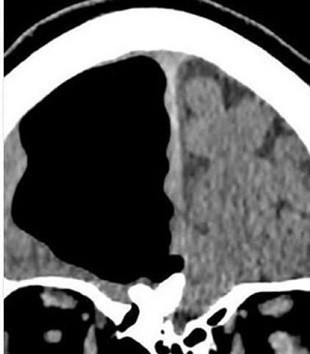

Galerinin tamamı için tıklayınızWashington Post’un dünyanın sayılı tıp dergilerinden BMJ’ye dayandırdığı haber İrlanda’da geçiyor. İsmi açıklanmayan 84 yaşındaki bir adamın baş ağrısı şikayetiyle hastaneye gitmesi sonrasında doktorlar rutin kontrolleri yaptı ve adamın röntgeninin çekilmesini istedi.